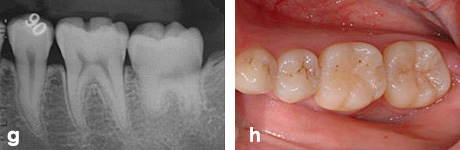

g、h : 移植後3年